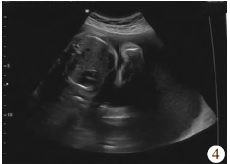

胎儿左眼距1.2 cm,右眼距1.2 cm,眼距1 cm(图2)。胎儿上唇中部唇腭回声缺失约0.9 cm(图3)。胎儿双肺显示不清,部分肝脏进入左侧胸腔,右移(图4)。胎儿右侧足底平面和小腿骨骼长轴切面可在同一切面内显示,右侧拇趾短与第2趾间距增大(图5)。超声诊断:①单胎,中孕,存活儿;②胎儿全前脑畸形;③胎儿全前脑面容(正中唇腭裂、眼距过近);④胎儿右足内翻合并拇趾短、草鞋脚;⑤胎儿左侧膈疝;⑥脐带胎盘入口处囊肿;⑦羊水过多。

图4胎儿胸部超声表现